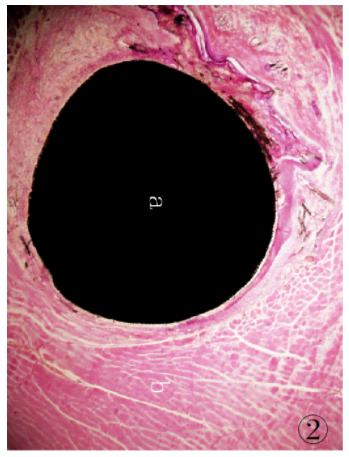

1.3.9 組織切片的染色將組織切磨片經(jīng)蒸餾水充分清洗后,參照文獻[5]的方法進行染色:蘇木精染液30 min,自來水充分沖洗,1%鹽酸乙醇分化30s,流水沖洗后再入溫水返藍,置伊紅染液5min,自來水沖洗,待組織切片自然干燥后經(jīng)Technovit 7210VLC封片,光鏡下觀察。制得的組織切片經(jīng)HE 染色后,細胞核、細胞質(zhì)著色對比鮮明,組織細胞形態(tài)清晰,可直接在光學(xué)顯微鏡下進行組織學(xué)觀察,可見植入的CF/PEEK 復(fù)合材料與周邊肌肉組織結(jié)合緊密( 圖2、3) ,植入的復(fù)合材料周圍可見新生纖維結(jié)締組織,纖維囊壁結(jié)構(gòu)已形成。

圖2 低倍鏡下埋置有CF/PEEK 復(fù)合材料的肌肉組織病理切片:a.試驗樣品CF /PEEK復(fù)合材料; b. 肌肉組織